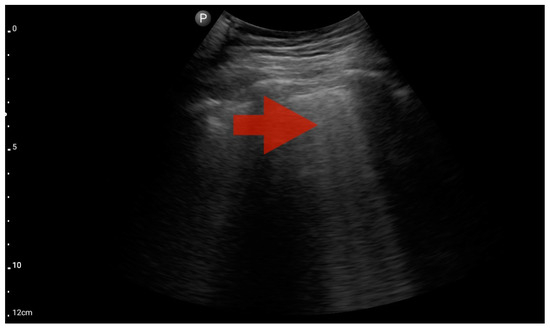

Right ventricle enlargement; position: parasternal long axis (FATE protocol). Sector probe; the right ventricle is marked with the red arrow, and a significant enlargement of the right ventricle is visible, with a shift of the interventricular septum towards the left ventricle, and an ultrasound picture suggesting pulmonary embolism (source: author’s material—DK).

Figure 14.